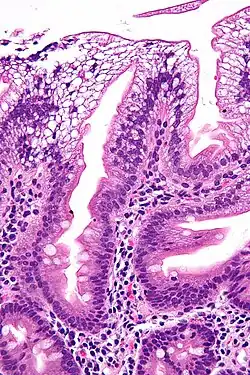

Micrograph showing enterocytes with a clear cytoplasm (due to lipid accumulation) characteristic of abetalipoproteinemia. Duodenal biopsy. H&E stain.

There is an absence of apolipoprotein B. On intestinal biopsy, vacuoles containing lipids are seen in enterocytes. This disorder may also result in fat accumulation in the liver (hepatic steatosis). Because the epithelial cells of the bowel lack the ability to place fats into chylomicrons, lipids accumulate at the surface of the cell, crowding the functions that are necessary for proper absorption.